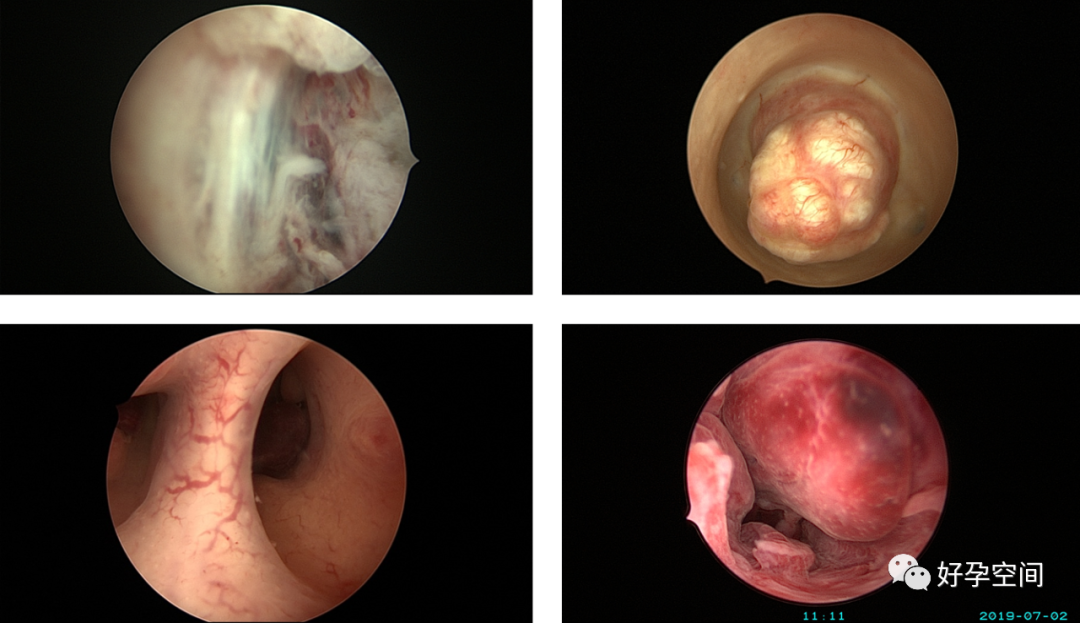

3、取环,环移位、环残留、环嵌顿、辅助安环、调整节育环位置。

宫内双环、三环、环残留、环卷曲在左侧宫角

宫腔粘连,节育环嵌顿

带环受孕

带环受孕左侧输卵管间质部妊娠

带环受孕左侧输卵管壶腹部妊娠